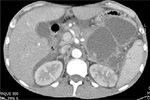

A large septated pseudocyst seen on abdominal CT (arrows outline diameter of the lesion)

Physical examination revealed bilateral foot drop and a palpable left upper quadrant mass. Abdominal CT scan (Figures 1-3) showed a pancreatic pseudocyst, a pancreatic pseudoaneurysm, and pancreatic inflammation that strongly suggested acute recurrent pancreatitis. The patient was admitted and treated for acute pancreatitis. Additional laboratory testing and serology found no infection. The fever resolved after several days and the patient was discharged to a rehabilitation facility.